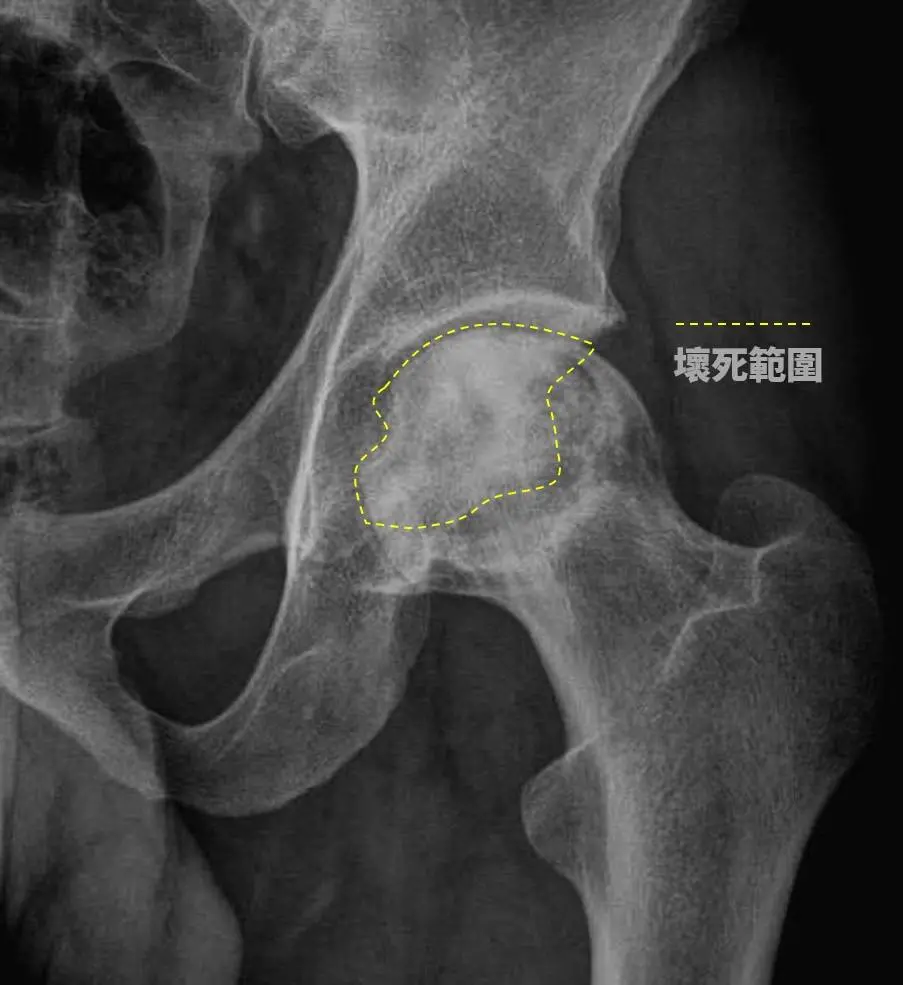

賴彥州指出,酗酒對骨骼的影響主要體現在骨細胞血液中的栓塞,影響脂肪代謝,進而引發股骨頭缺血性壞死。這2位患者的情況顯示,股骨頭已出現半月狀,即軟骨下方的骨頭已經壞死,且關節面已崩塌,為改善患者生活品質,建議進行半人工髖關節置換手術,手術後,兩位患者康復良好,不再感到疼痛,能夠自如地行動。然而,醫師提醒患者在康復期間需謹慎,避免過度彎腰、蹲下、提重物或跑跳,以確保手術效果最大化。